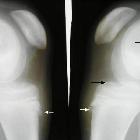

Osteochondritis

dissecans and Osgood Schlatter disease in a family with Stickler syndrome. Patient 1: Anteroposterior knee radiograph at age of 15 years shows osteochondritis dissecans of the distal femoral epiphysis with areas of evident epiphyseal necrosis (arrows).

dissecans and Osgood Schlatter disease in a family with Stickler syndrome. Patient 1: Coronal MR image of the knee at age of 17 years shows progressive and lesion from the underlying subchondral bone with apparent anterior separation of the articular surface with evidence of epiphyseal friability. Note the bony fragment had resulted in a concave crater on the femoral condyle with steeply sloping edges (arrows)